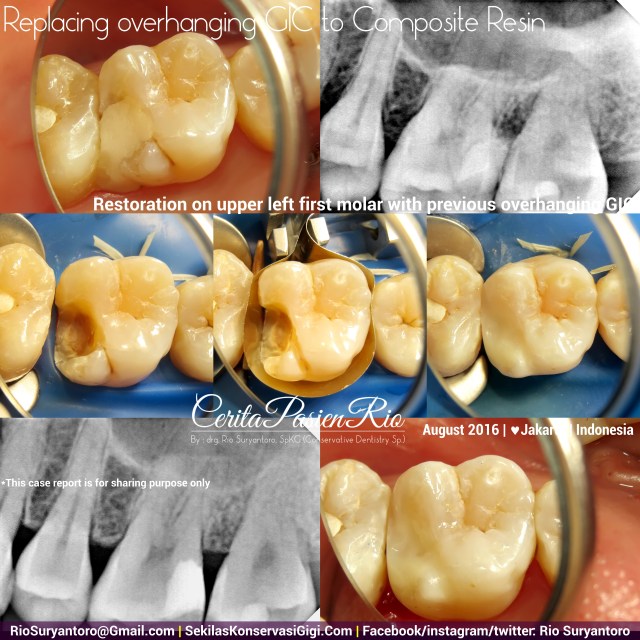

Replacing old and improper GIC Filling

The good embrasure is one of the important thing to be achieved in managing a class II restoration. An overhanging restoration is considered failed in mimic dental anatomy, leads to marginal gingivitis, and periodontitis, also secondary caries due to expected micro leakage.

Here i got this patient complaining her upper left first molar that has been filled for two weeks and still feeling painful. After receiving proper inform consent, I started my dental treatment.

First I removed all the old filling (GIC) , then I put rubber dam (sanctuary rubber dam clamp and sheet) prior to composite filling restoration. I put greater curve matrix and wood wedge, placed bulkfill composite (Filtek bulkfill – 3M) then I put universal composite (Vit~L~essence – Ultradent). Polished with soflex (3M) and enhance (dentsply).

X-ray examination with Vistaray 7.1 (Durr) showed homogenously filled cavity with intact margin from composite resin and tooth structure.